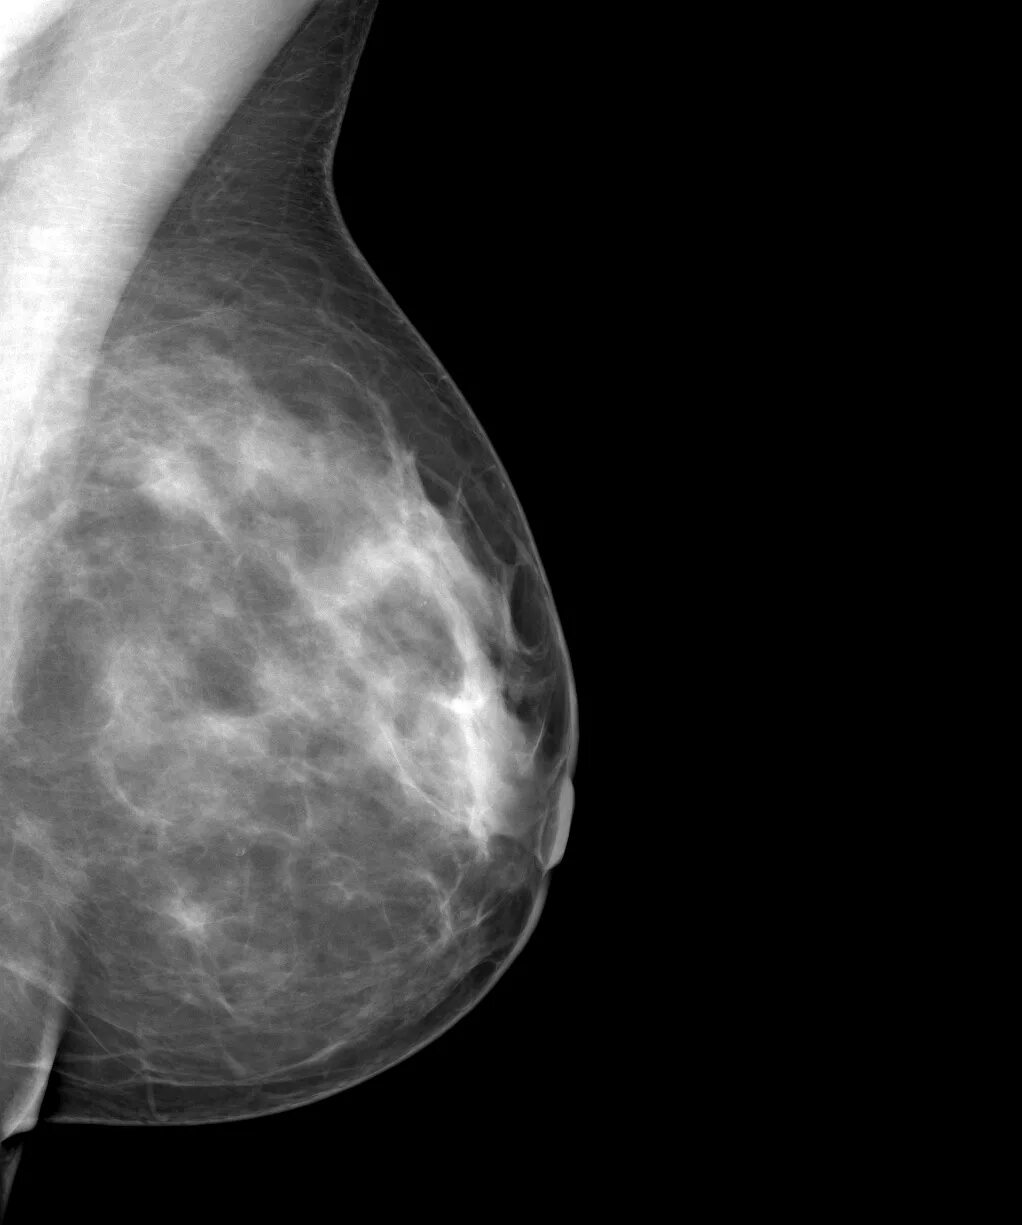

Инволютивные изменения в молочной железе